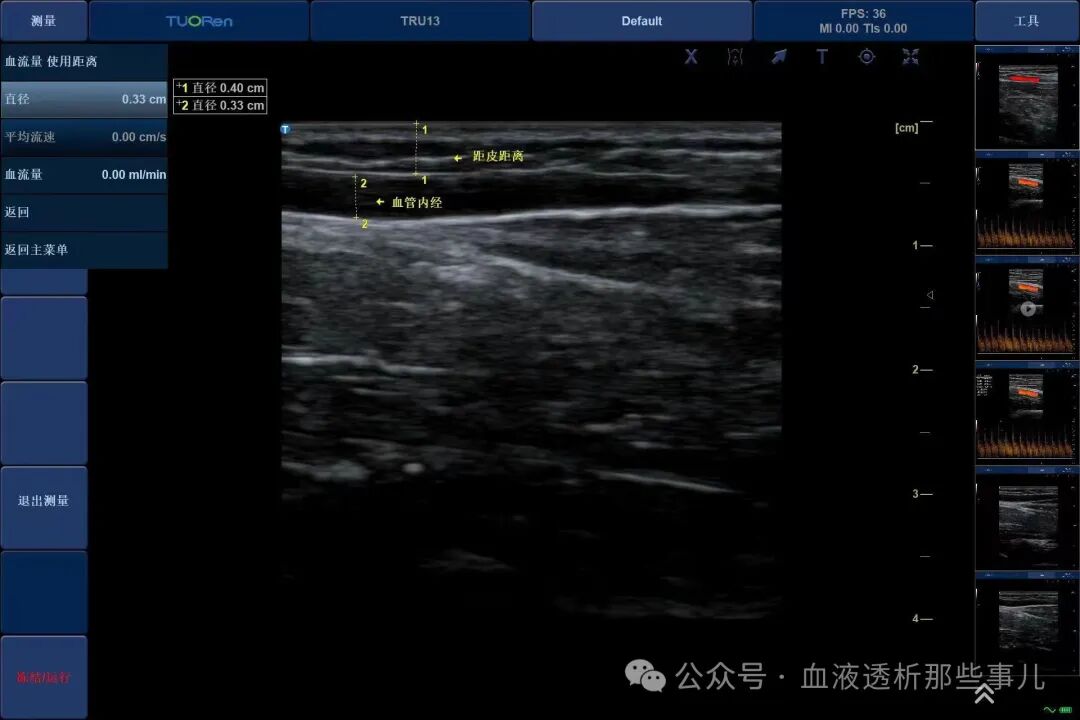

*测量距皮深度与血管内径